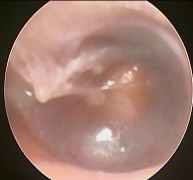

Hình ảnh nội soi tai

Ảnh 9 MN lõm, xanh MSBA. 1806217636 |